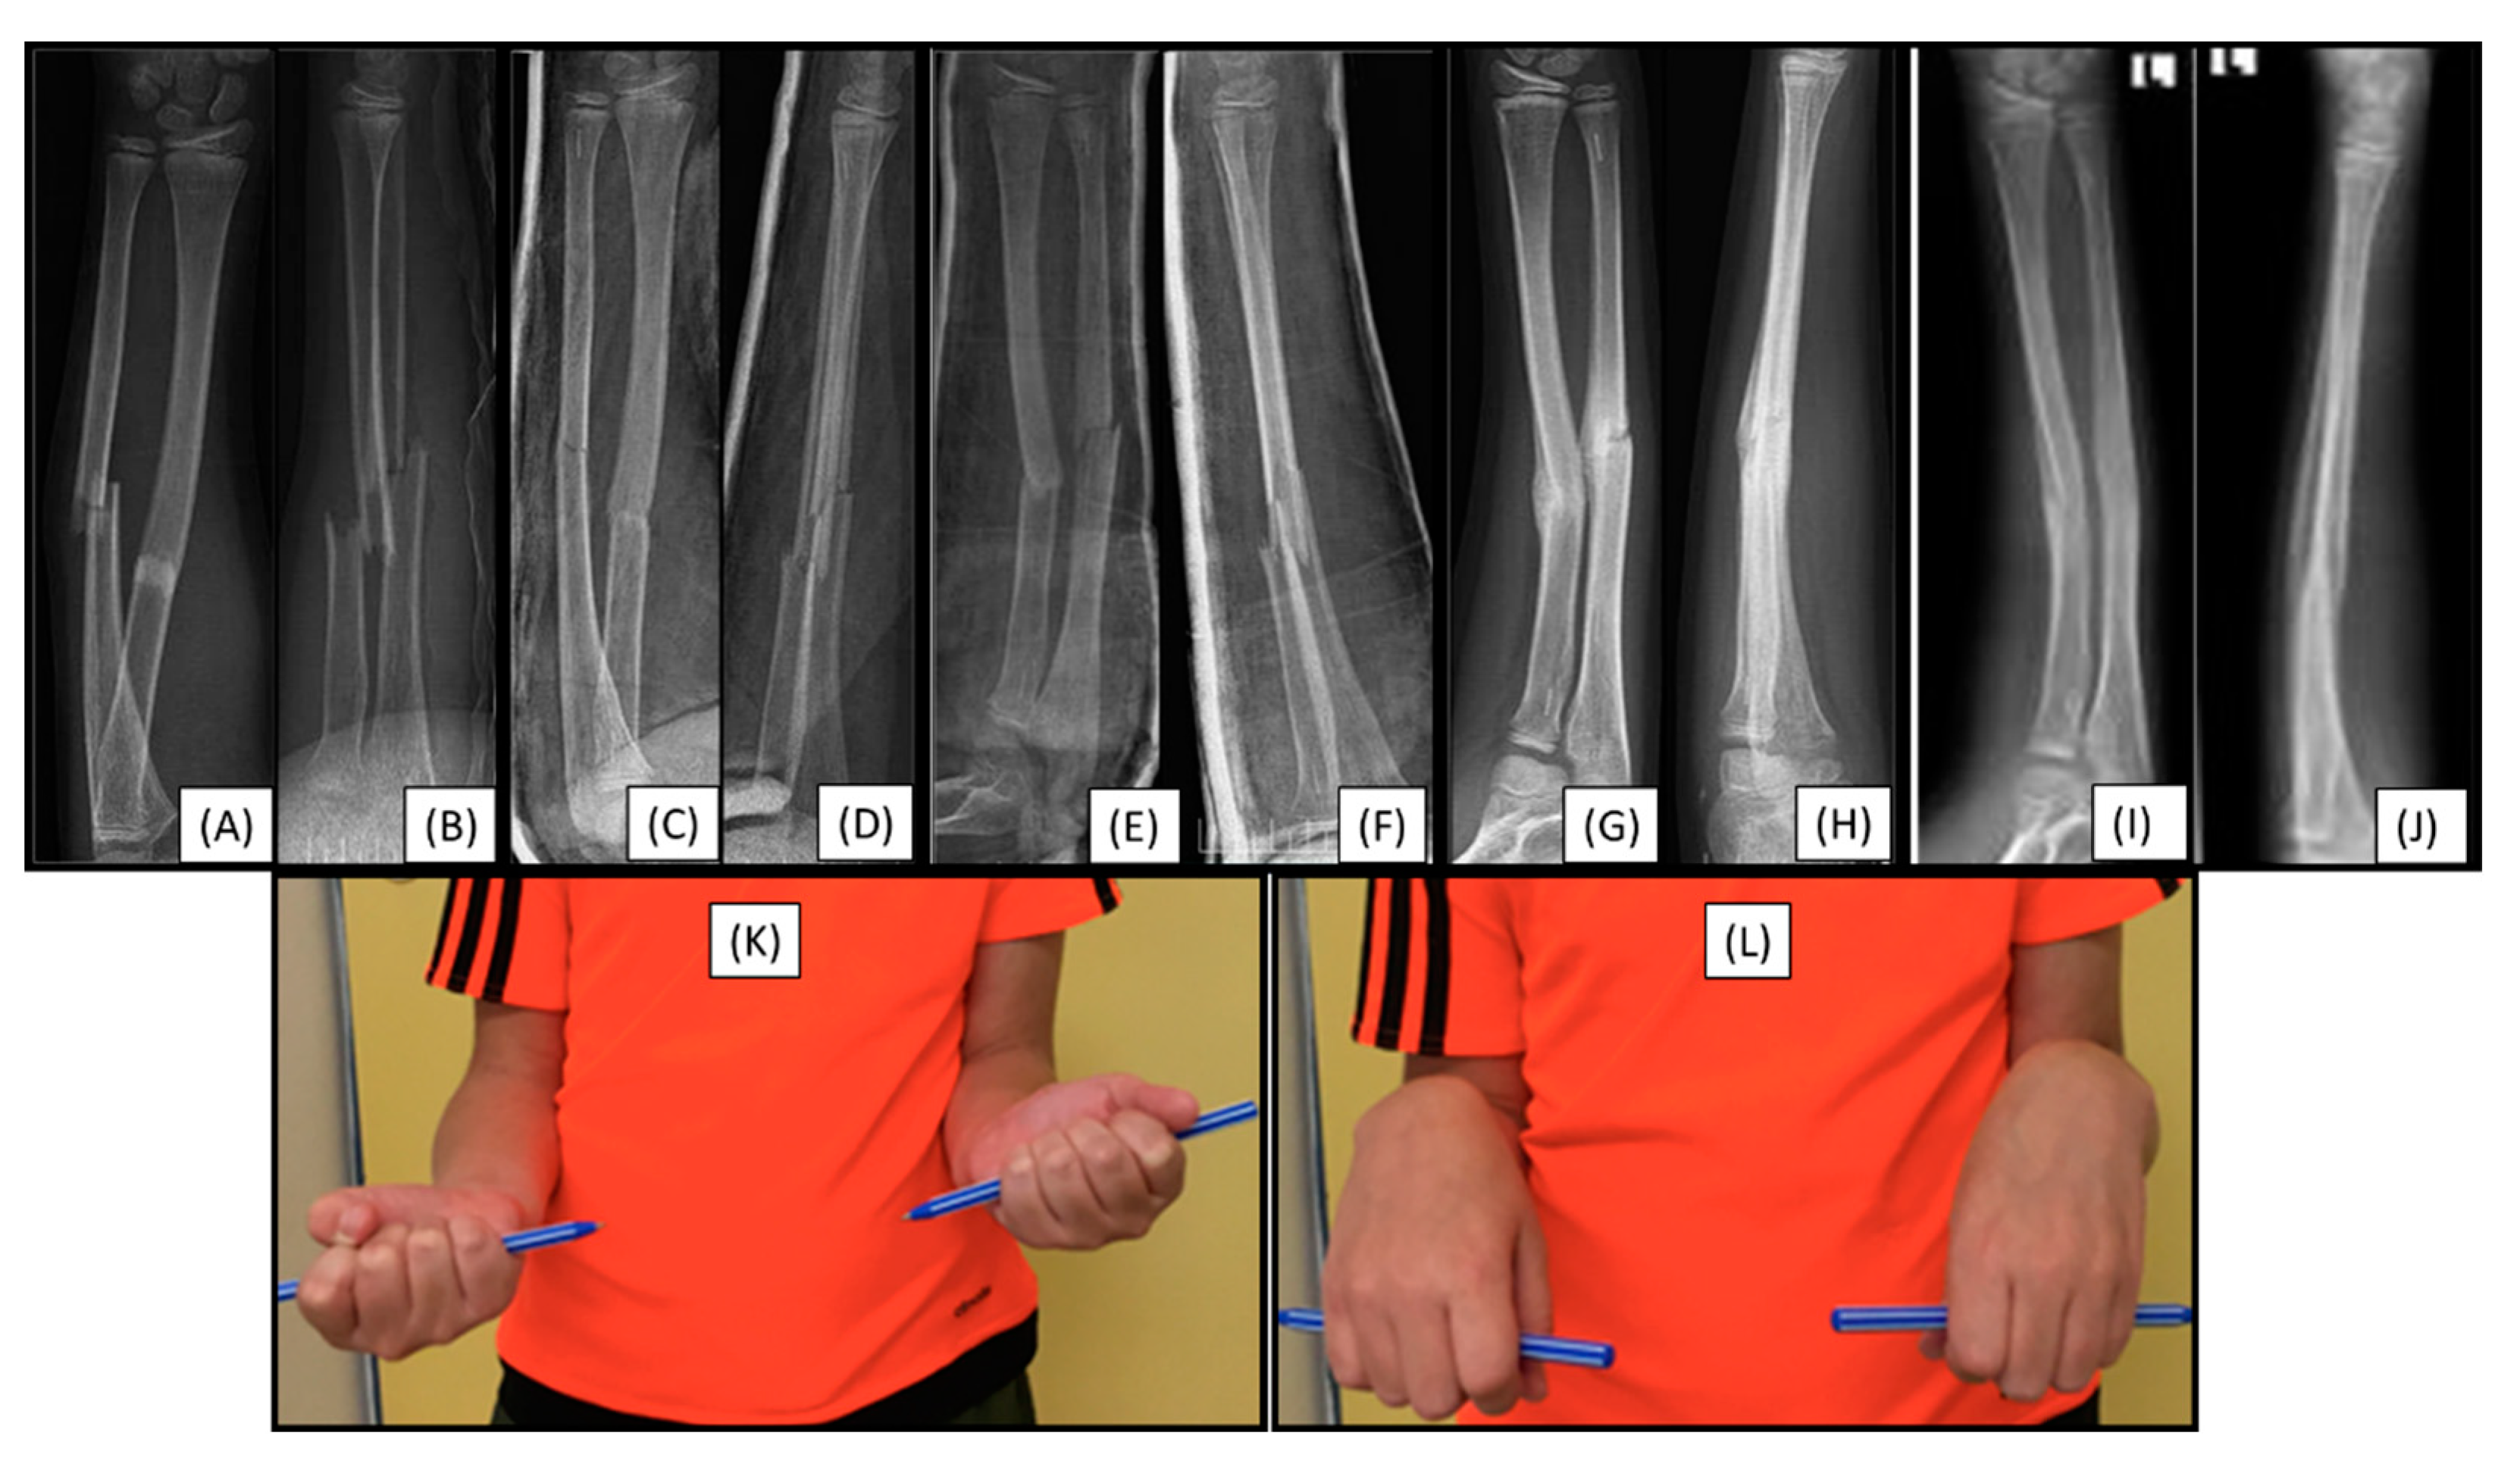

Secondary malalignment was observed in a 12-year-old patient who had sustained a both-bone proximal diaphyseal forearm fracture (22-D/4.1.) in the left arm (Figure 5(A-B)). These fractures were reduced and stabilized with PLGA BINs. Postoperative visualization initially showed adequate alignment (Figure 5(C-D)).

Control X-rays performed one week postoperatively showed a mild secondary malalignment, with shaft axis angulation of <15° (Figure 5(E-F)). On an imaging follow-up, eight weeks after surgery, the angulation persisted, and a callus had formed at the fracture sites (Figure 5(G-H)). Clinically, the patient showed a 10° deficit in supination of the left wrist (Figure 5(K)), with no deficit in pronation (Figure 5(L)). The child is currently being followed up.

Figure 5. Preoperative (from AP (A) and lateral (B) views), and immediately postoperative (AP (C), lateral (D)), control radiographs. Follow-up X-rays were taken one week (AP (E), lateral (F)), eight weeks (AP (G), lateral (H)), and six months postoperatively (AP (I), lateral (J)), exhibiting good callus formation and remodeling. The patient showed a 10° deficit in left wrist supination (K), with no deficit in pronation (L).